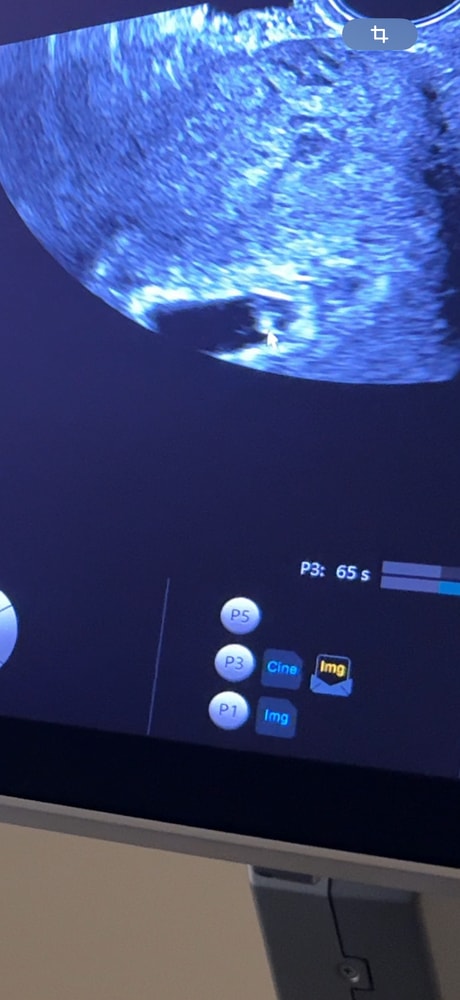

26ДПП УЗИ

Девочки привет 🌹 сегодня повторно была на узи , напомню , что на 21ДПП была на первом УЗИ : нашли ПЯ 10,5мм , ЖМ 3,9мм , эмбрион не лоцировался , думала сегодня уже должны были найти эмбрион , но он спрятался за ЖМ , главное увидели пульсацию и я ее видела , не знаю можно сюда видео загрузить или только фото.

сегодня ПЯ 21,6 , ЖМ 6,1 , эмбрион доуируется , ЧСС 120 уд.